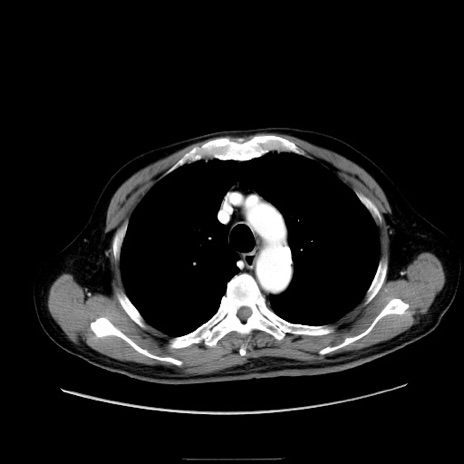

症例30(横断像)

【症例】80歳代男性

【主訴】臍周囲痛

【現病歴】約6時間前から臍下部痛が出現。次第に腹部膨隆・背部痛も生じてきたため来院。背部痛の場所は変化しない。

【身体所見】意識清明、BT 36.3℃、BP  131/87mmHg、P 87bpm、SpO2 100%(RA)、臍周囲自発痛・圧痛あり、反跳痛なし、自発痛部位に一致して板状硬あり、腹部膨隆、腸雑音減弱、CVA tenderness両側陰性。

【データ】WBC 19600、CRP 0.33

冠状断像